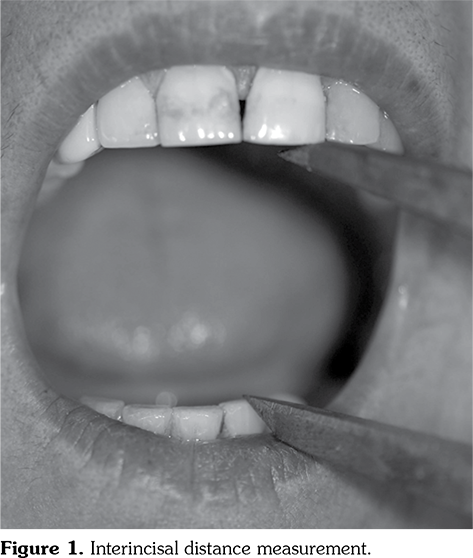

Factors affecting ID were evaluated with linear regression analysis. Sex, disease type, mRSS, FTP distance, telangiectasia, calcinosis, ILD, cardiac involvement, and Medsger scores were included in the regression analysis. According to the stepwise procedure, sex, presence of ILD, FTP distance >0 mm and mRSS were found to be the most effective factors on mouth opening (Figure 2, Table 4). Coefficients were adjusted according to age. A formula was constituted to predict the maximal mouth opening of the patients. According to the formula, being male was associated with an increase of 6.14 mm, the presence of ILD with a decrease of 3.19 mm, every 10 mm increment in mRSS with a decrease of 3.72 mm, and FTP distance >0 mm with a decrease of 5.13 mm in mouth opening.